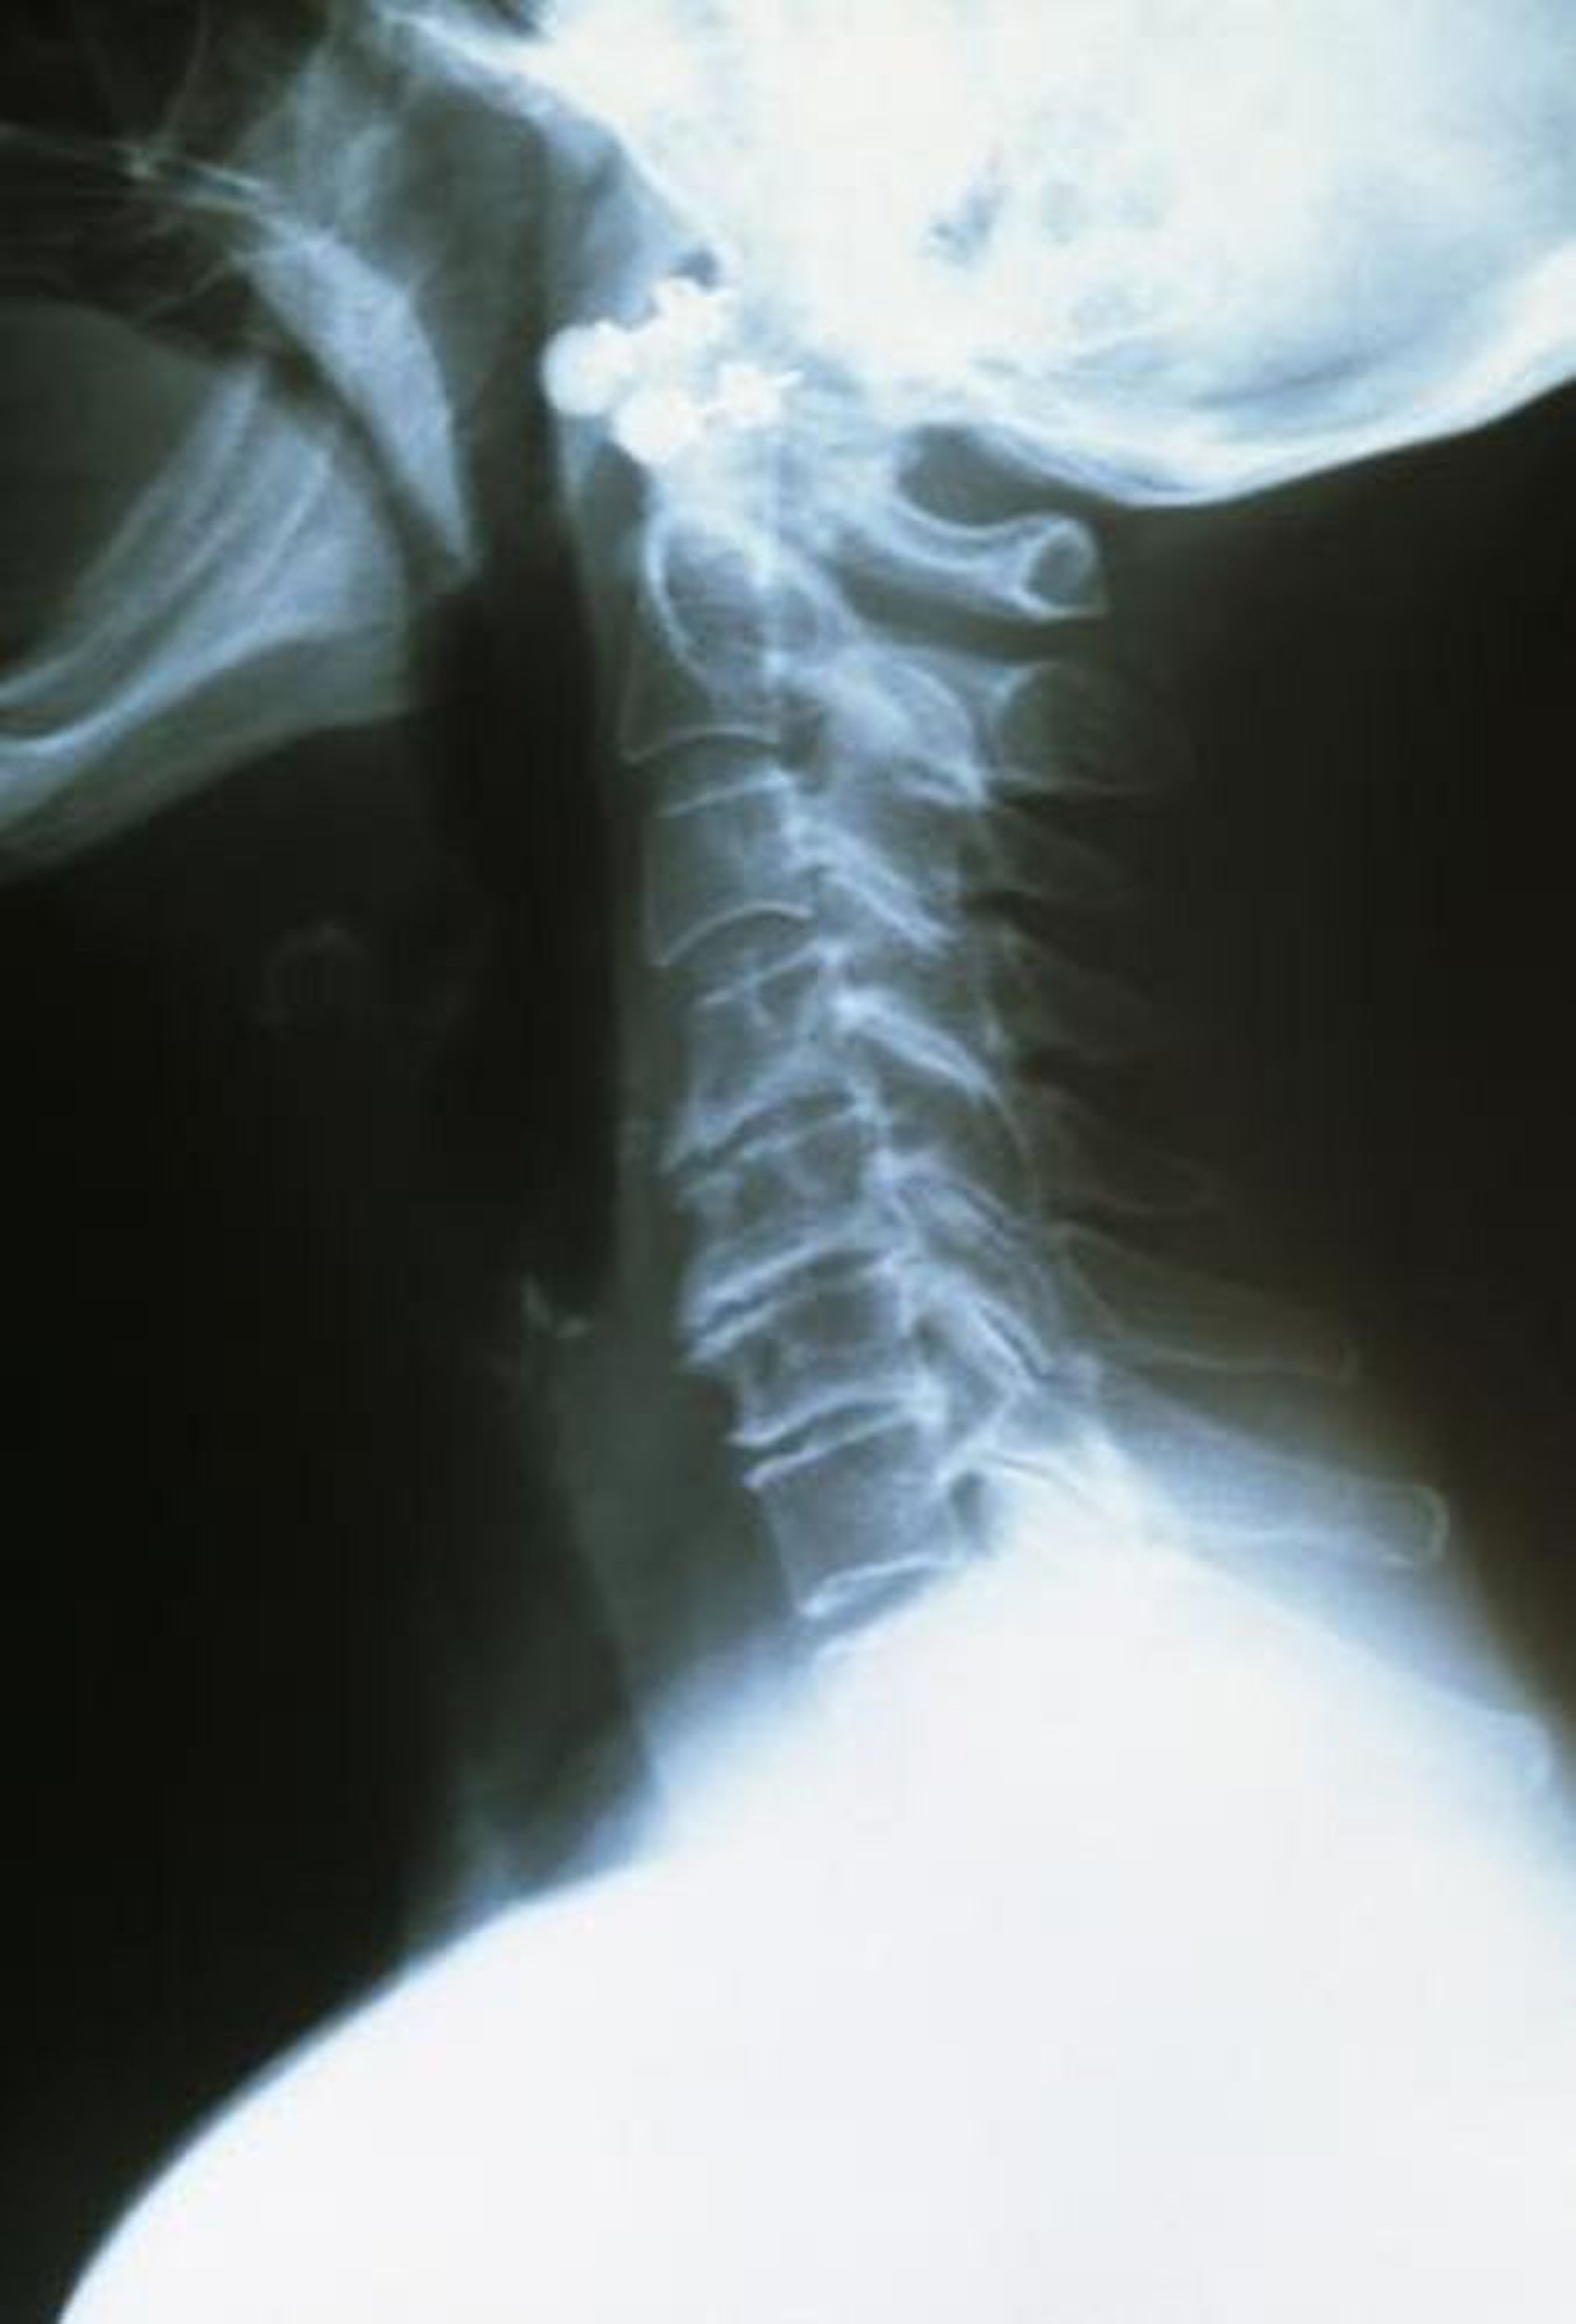

Artrosis cervical

Las vértebras cervicales superiores son sanas, están bien espaciadas y tienen bordes lisos. Las vértebras inferiores artríticas están más juntas y tienen bordes ásperos e irregulares.

DR P. MARAZZI/SCIENCE PHOTO LIBRARY